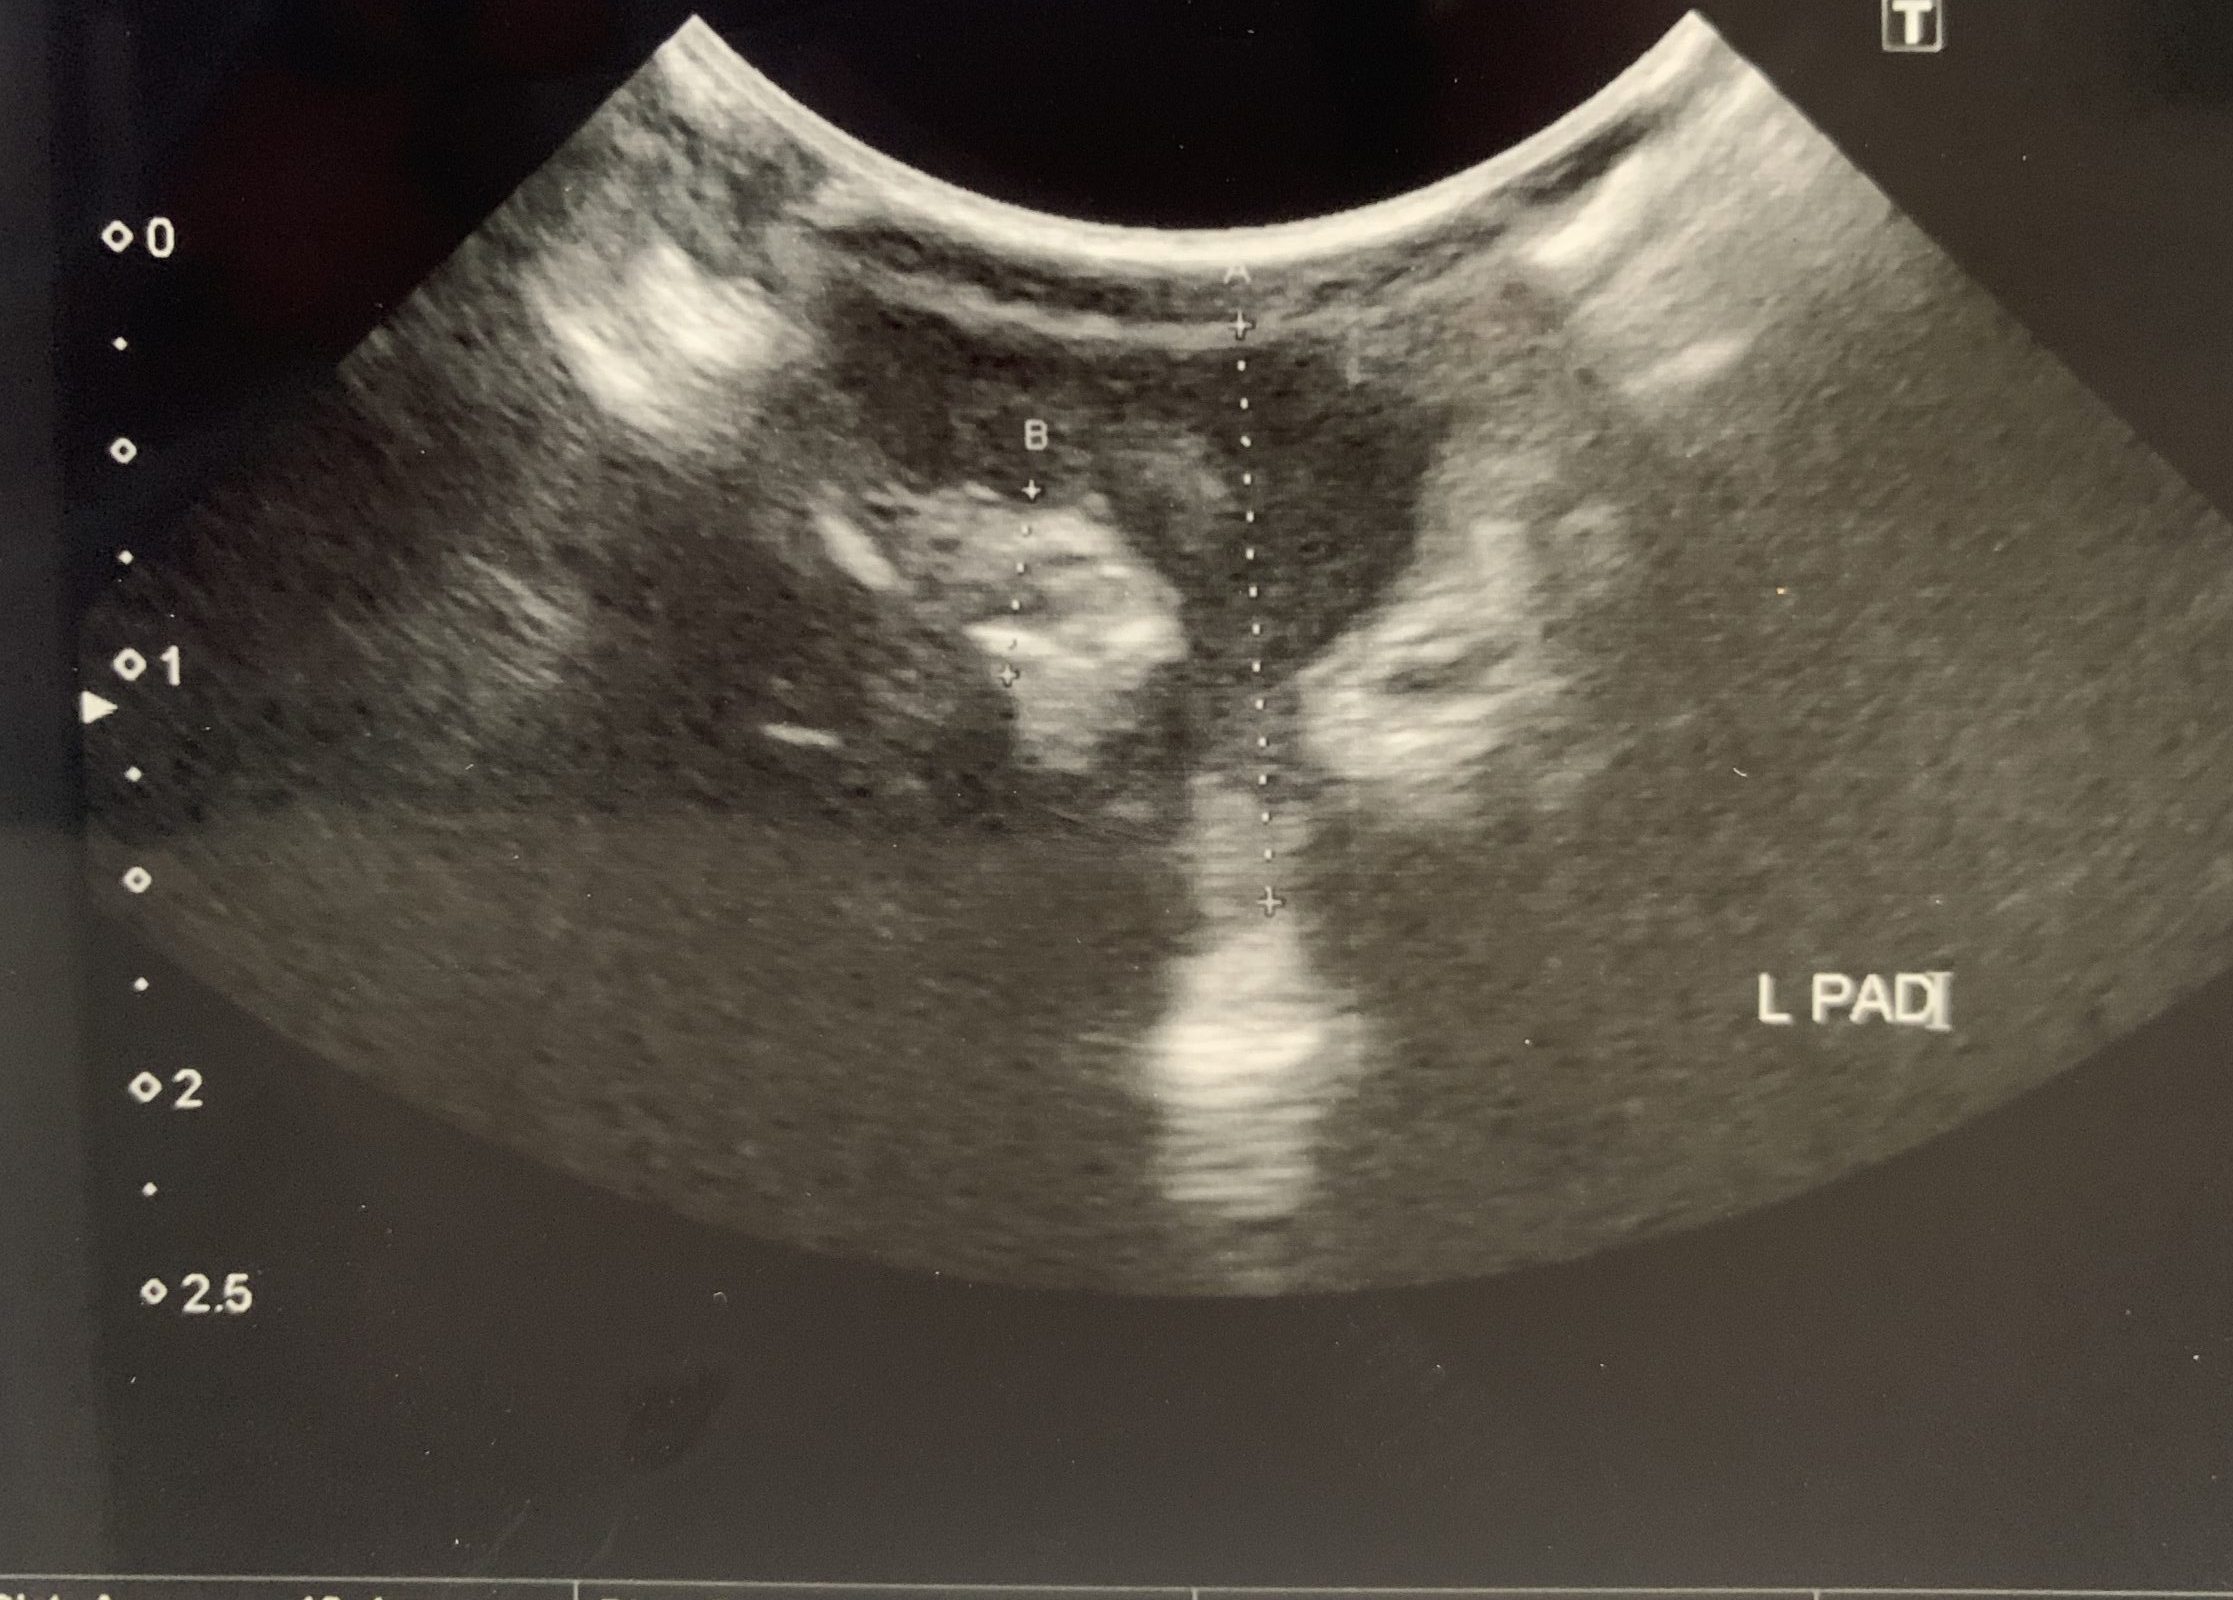

診断技術の向上により、臨床医が孤立性形質細胞腫を特定するのに役立ちました。現在、この状態の検出に役立つツールには次のものがあります。

- 画像検査。医師が形質細胞腫の存在を特定するのに役立ちます。

これらの結果を使用し、診断基準と比較することは、医師が状態の程度を判断するのに役立ちます。さらに、骨髄穿刺や画像検査などの検査は、多発性骨髄腫を示す可能性のある多発性形質細胞腫の進行リスクや存在を特定するのに役立ちます。